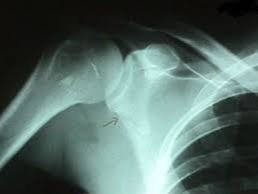

상완골 골절은 팔의 기능을 담당하는 핵심 뼈가 손상되는 질환으로, 단순 골절부터 분쇄 골절까지 다양한 형태로 발생합니다. 특히 교통사고나 낙상, 스포츠 손상 등 외상에 의해 발생하는 경우가 많으며, 치료 과정은 단순히 뼈를 붙이는 것에서 끝나지 않고 재활까지 이어지는 장기적인 관리가 필요합니다.

상완골은 어깨부터 팔꿈치까지 이어지는 긴 뼈로, 어깨관절과 팔꿈치관절을 연결하는 핵심 구조입니다. 이 부위가 골절되면 단순한 통증을 넘어서 팔의 움직임 자체가 제한되며 일상생활에 큰 불편을 초래합니다.

- 근위부 골절: 어깨 관절 근처 골절

- 간부 골절: 중간 뼈 부분 골절

- 원위부 골절: 팔꿈치 근처 골절

상완골 골절은 반드시 수술이 필요한 것은 아니며, 골절 상태에 따라 보존적 치료와 수술적 치료로 나뉩니다.

- 금속 핀, 플레이트, 나사 고정

- 골절이 심하거나 어긋난 경우

- 기능 회복을 위해 정렬이 중요한 경우

특히 핀 고정 수술은 골절 부위를 정확히 맞추고 빠르게 안정화할 수 있다는 장점이 있습니다. 다만 수술 이후에도 재활이 반드시 병행되어야 정상적인 기능 회복이 가능합니다.